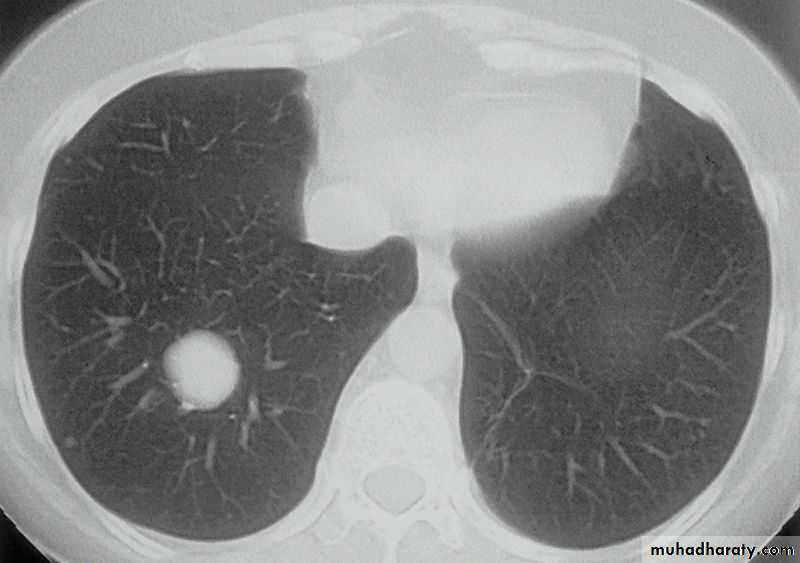

History: dyspnea, weight loss, dehydration with poor immunity